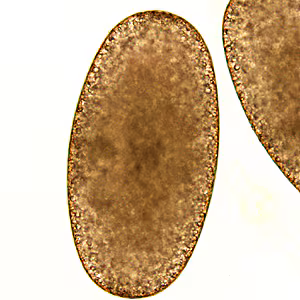

A 34-year-old man presented to his health care provider with a lesion with a dark center on his right hallux (big toe) that was inflamed and painful. Travel history included Panama and Ecuador one month prior. During the examination, the physician collected fluid that was exuding from the center of the lesion. The exudate was examined microscopically; Figures A–C shows what was observed at 20x, 40x, and 100x, respectively. The objects of interest measured on average 600 micrometers. What is your diagnosis? Based on what criteria?

Figure A